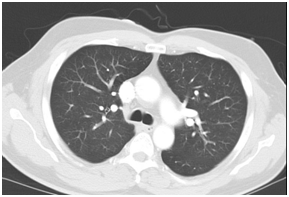

In view of the elevated Troponin I, the patient was initially treated as for Non-ST elevated myocardial infarction (NSTEMI). He was immediately started upon dual anti-platelet therapy together with low molecular weight heparin and subsequently underwent an emergent coronary angiogram which showed minor coronary artery disease. Computed Tomography of Pulmonary Arteries was also performed which showed no evidence of pulmonary embolism (Figure 2). The anti-platelet and low molecular weight heparin was then stopped. However, his gastro-intestinal symptoms worsened and he started to spike a temperature once more in the ward. He complained of persistent abdominal pain despite bowel clearance with laxatives. Computed Tomography of Abdomen and Pelvis was performed. The result showed long segment rectal wall thickening seen with peri-rectal fat stranding which was initially thought to be related to aggressive laxative consumption , but malignancy and infection should be ruled out with suggestion of endoscopy; extensive omental fat stranding, most prominent in the upper abdomen abutting the anterior wall of the transverse colon where there was thickening of the anterior transverse colonic wall to rule out possibility of underlying malignancy; peritoneal fat stranding and nodularity seen with minimal ascites; small volume but rounded inferior mensenteric and para-aortic lymph nodes seen.

The CT thorax and CT pulmonary angiogram showed marked pulmonary infiltrates and thrombi. There was a thombus in the segmental right lower lobar pulmonary area, with an infracted region in the right lung base. There was also another thrombus in the anterior segmental branch of the left lower lobe pulmonary artery. Subsequently, the patient suffered from opthalmoplegia due to stroke in the ward. The MRI/MRA revealed acute infarcts in the left cerebellum, occipital lobe and left medial longitudinal fasciculus. He also developed gut vasculitis and a perforated transverse colon (Figure 3) (Figure 4). The findings on CT abdomen and pelvis were consistent with that of a small/medium vessel vasculitis. Multifocal ischemic colitis was seen involving the right lateral and posterior walls of the rectum as well as the inferior wall of the mid transverse colon with suggestion of perforation on both sides. The superior rectal artery was thrombosed as well. The patient then underwent emergency laparotomy with resection of small bowel and stoma creation. Post-operatively recovered well and was discharged two weeks after. Currently he is on follow up with rheumatologist, neuroopthalmologist and general surgeon (Figure 5).

Figure 5CT Pulmonary Angiogram: A few non- specific pulmonary nodules are seen e.g. in the anterior segment of the right upper lobe.

Figure 5CTPA: Thrombus in the segmental right lower lobar pulmonary artery, and anterior segmental branch of the left lower lobe pulmonary artery. There is right ventricular strain and infarct in the right lung base.